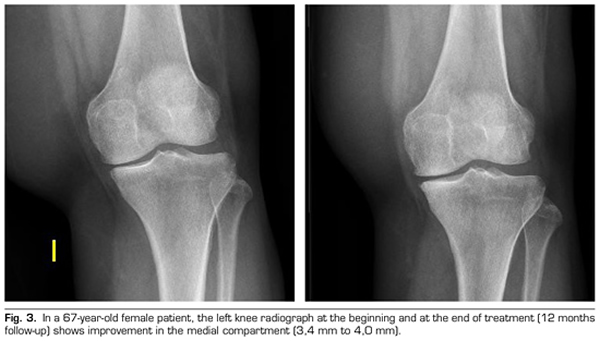

Regarding the radiological variables, when evaluating 53 out of the 115 patients who completed one year of follow-up after ozone treatment, it was observed that the internal compartment increased significantly by 4.12 ± 1.41 mm to 4.4 ± 1.35 mm (p = 0.0008) and the external compartment increased from 6 ± 1.37 to 6.16 ± 1.4 mm (p = 0.0753) (Table II). Two clinical cases are presented as a sample of the radiological change in the internal and external compartments (Figures 2 and 3).

After a year of follow-up with radiological controls on 53 out of the 115 patients in the study, ozone (O2-O3) has been able to increase the minimum joint space of the medial compartment (from 4.12 to 4.44 mm) and the lateral compartment (from 6.0 to 6.16 mm), reversing knee osteoarthritis in our case series. This finding suggests the disease modifying effect of ozone (O2-O3) on knee osteoarthritis, findings that is consistent with the recently reported by Fernández-Cuadros et al. (9).